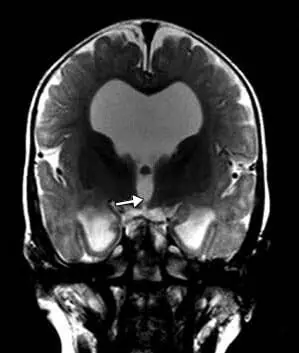

頭部磁気共鳴映像法では、テント上水頭症、視交叉陥凹のバルーニング、薄い脳梁、側脳室および第3脳室の拡張、透明中隔の欠如、および脳の低髄鞘化が明らかになった(図2)。

図2. 磁気共鳴画像法T2強調矢状画像。 脳梁は薄かった。 磁気共鳴画像法T2強調冠状断像。